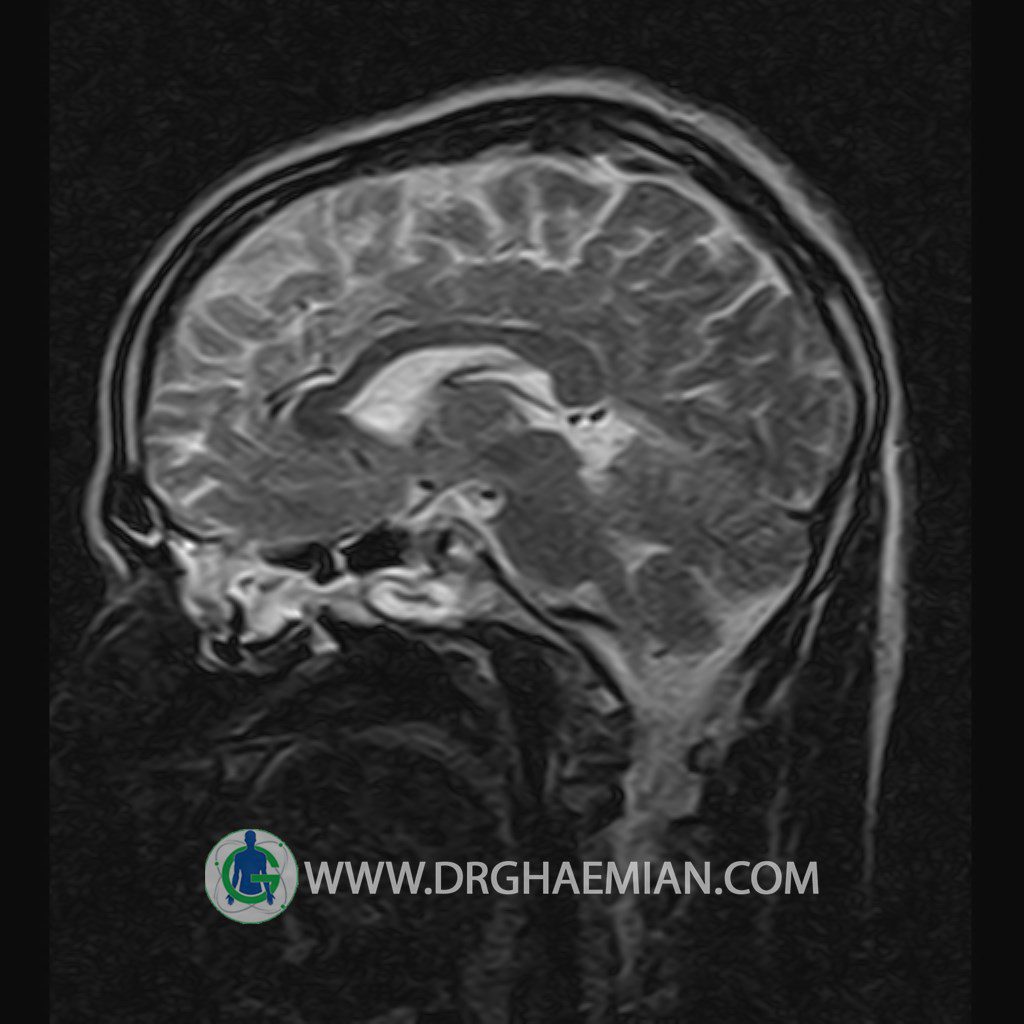

پزشکان اغلب از تصویربرداری ام آر آی برای تشخیص و درمان عارضه های پزشکی که فقط با استفاده از اشعه ایکس یا میدان مغناطیسی و امواج رادیویی قابل مشاهده است، استفاده می کنند. دستگاه ام آر آی تصاویر دقیق از ساختار های داخلی بدن ایجاد می کند. در این کیس یک میکروآدنوم در هیپوفیز بیمار مشاهده می شود.

HYPOPHYSIS MRI

(with and without contrast)

Technique: Axial , coronal T1 , Axial , coronal , sagittal T2 , Axial, coronal T1 post Gd & 64 dynamic thin coronal slices.

The sphenoid sinus is clear and pneumatized .

– Small hypoenhancing mass lesion ( 3 x 4 mm ) in posterior of pituitary stalk suggestive for micro adenoma

– Mucosal thickening in ethmoid & maxillary sinuses

is seen